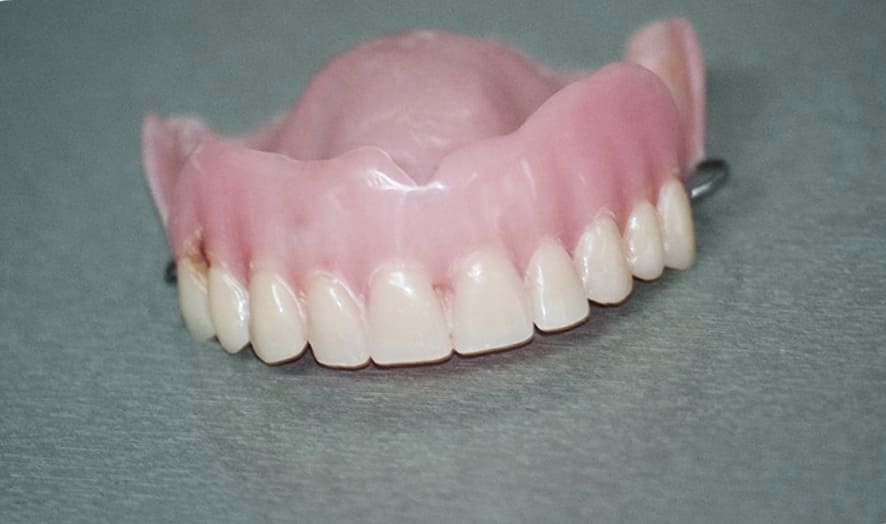

임플란트 가격이 해결되면 사실상 틀니를 할지 고민을 하지 않아도 되는데요. 틀니를 하게 되면 임플란트처럼 복잡한 수술은 안해도 되지만 매일 같이 탈착을 해야하는 번거로움이 있고 아주 깨끗하게 위생 관리를 해야 합니다. 이러한 점에 불구하고 임플란트에 비해 저렴하고 신속하기 때문에 아직까지 노인 분들은 틀니를 선호하십니다.

하지만 잇몸 위에 얹어서 사용하는 만큼 밀착력이 뛰어나지 않아 쉽게 분리가 되며 3~4년이라는 짧은 수명을 갖고 있어 교체 비용을 생각하면 임플란트와 크게 차이가 나지 않습니다. 더 나아가 틀니를 탈부착하면서 잇몸뼈가 손상할 수 있기 때문에 비용, 번거로움, 잇몸 건강을 위해서라도 임플란트를 하는 것을 추천합니다.